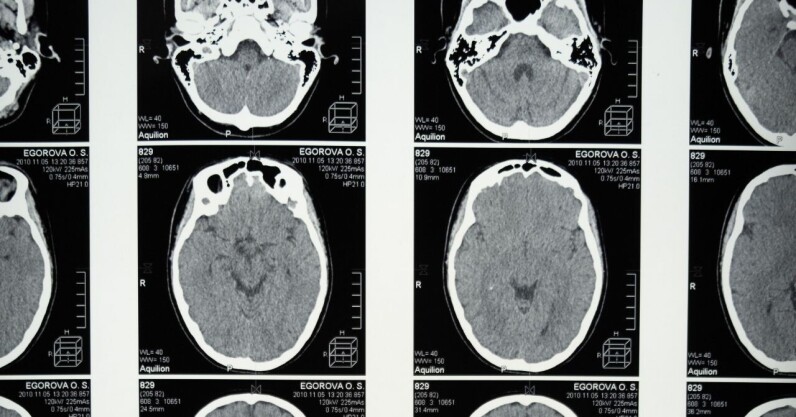

Scientists at Cambridge University have developed an AI system that they believe could diagnose dementia from a single brain scan. Pre-clinical testing suggests the tech can spot signs of dementia years before symptoms develop. The system is now being evaluated in clinical trials. Up front: Doctors currently diagnose dementia through multiple cognitive tests and brain scans. This process can take between four to 12 weeks, according to the Alzheimer’s Society. The AI tool was designed to provide quicker diagnoses and predictions on how the condition will develop. The system’s algorithm searches for patterns in brain scans that neurologists can’t detect. These are then matched…